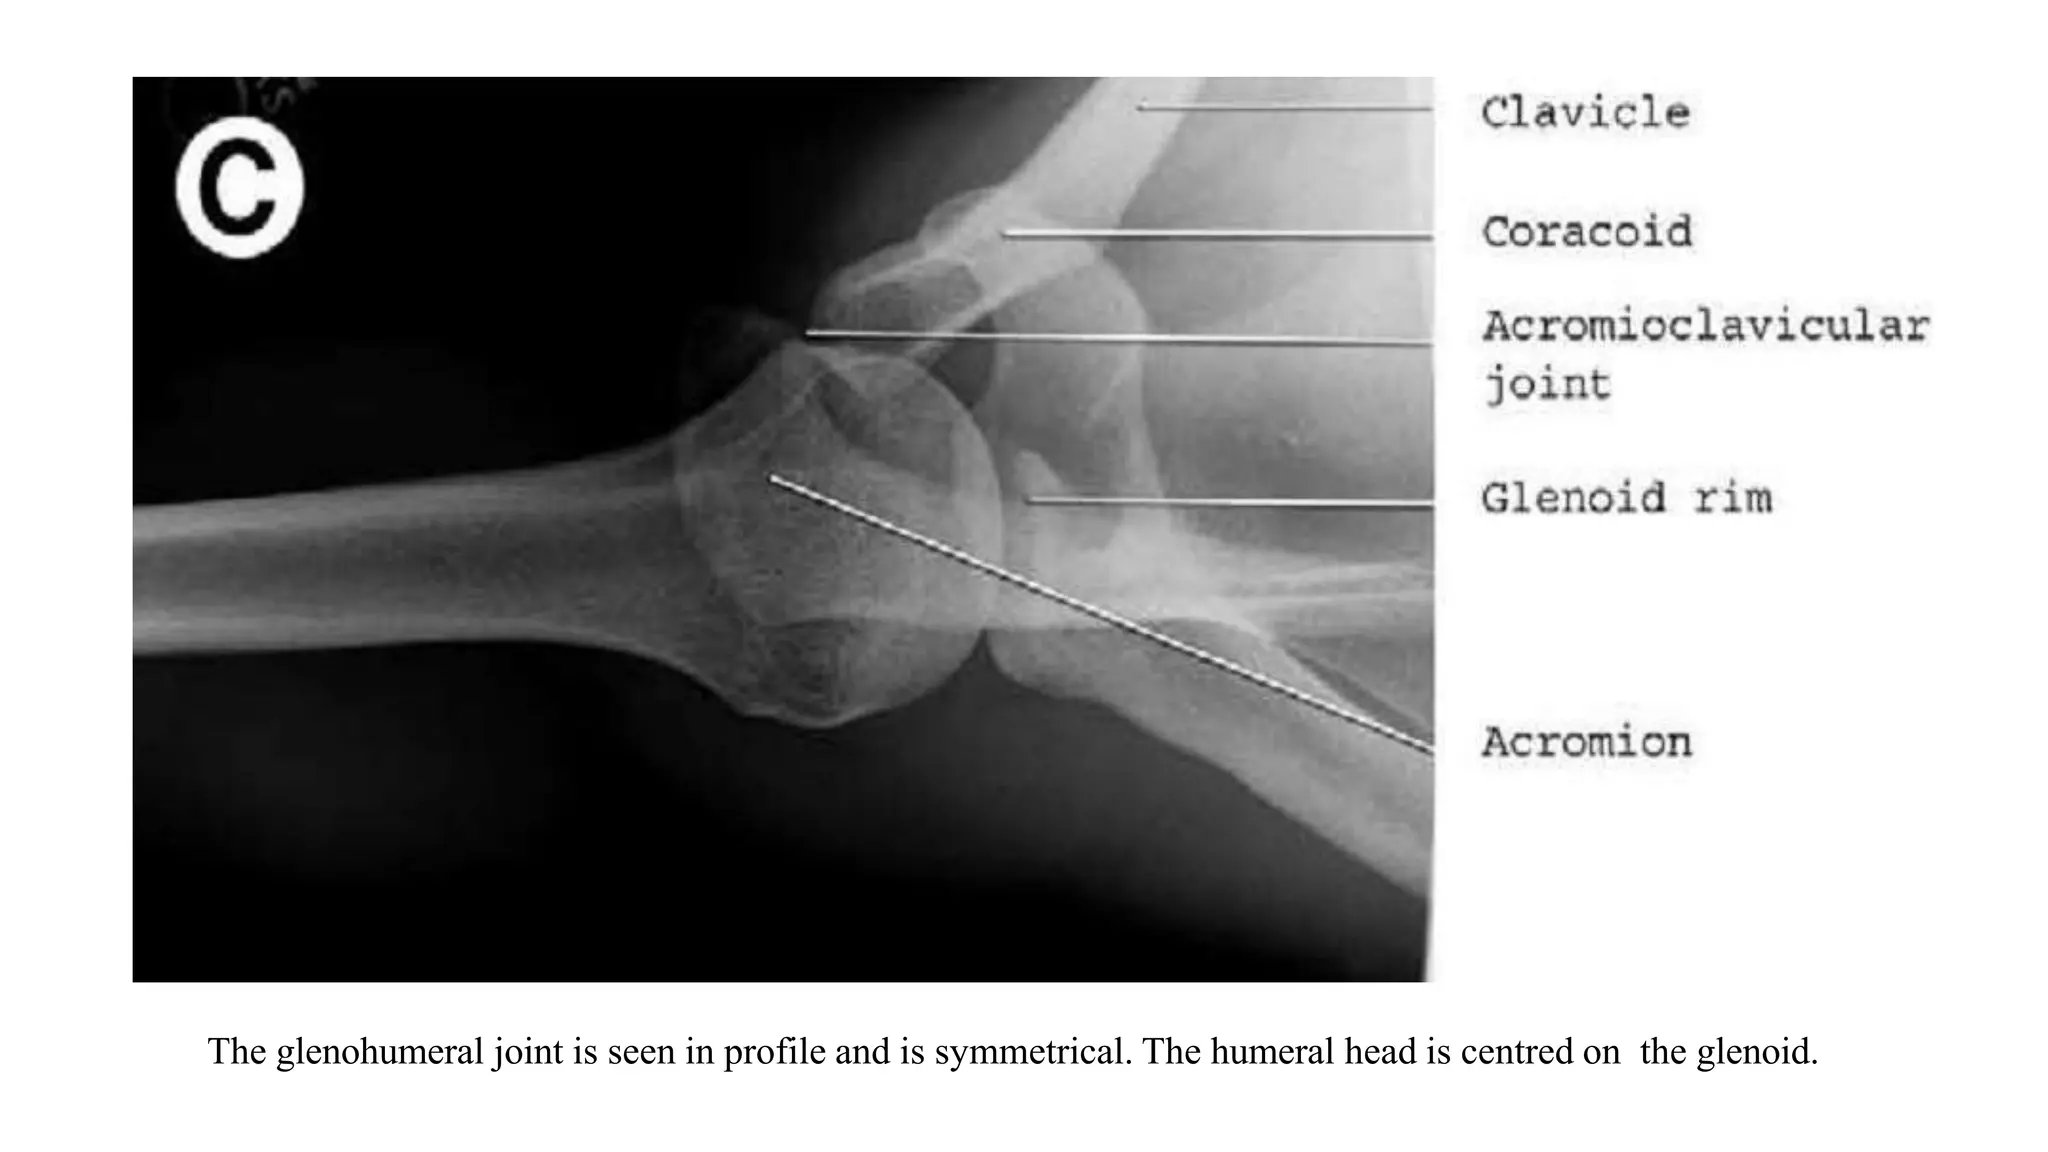

4. AXILLARY VIEW

• Axillary view is a tangential view of the glenohumeral joint from below.

• Demonstrates: glenohumeral joint narrowing (best view), Os Acromionale, glenoid version, glenoid erosion,

humeral head subluxation.

• Helpful for: determining the amount of acromion which remains in patients who have undergone previous

surgery; relation of humeral head to glenoid; Hill-Sachs lesions, Os Acromionale, Acromioclavicular Arthritis,

Shoulder Dislocation, osseous Bankart fracture involving the anterior glenoid rim.

• The radiographic quality is often very limited because of the rapid change of overlying soft-tissue

density.

Position: Patient seated at side of radiographic table or supine with the arm abducted 90º and axilla over the cassette.

Beam: angle 5°-10° toward the elbow, central beam directed at the shoulder joint/humeral head.

The glenohumeral joint is seen in profile and is symmetrical. The humeral head is centred on the glenoid.